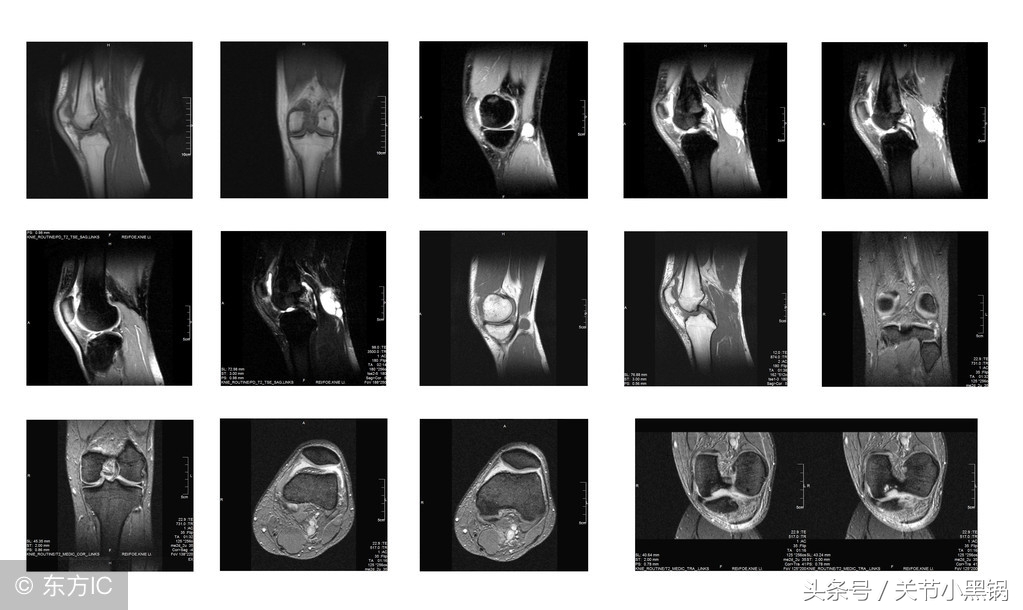

2、磁共振(MRI)检查较少用!

如果患者有外伤史,或者医生怀疑患者有关节韧带撕裂、半月板损伤等这些情况,就会建议患者做磁共振检查(MRI)。MRI还可以用于排除肿瘤等,价格也比普通的X光片贵的多,平扫MRI850++,增强MRI1400++,X光片只要120+左右。